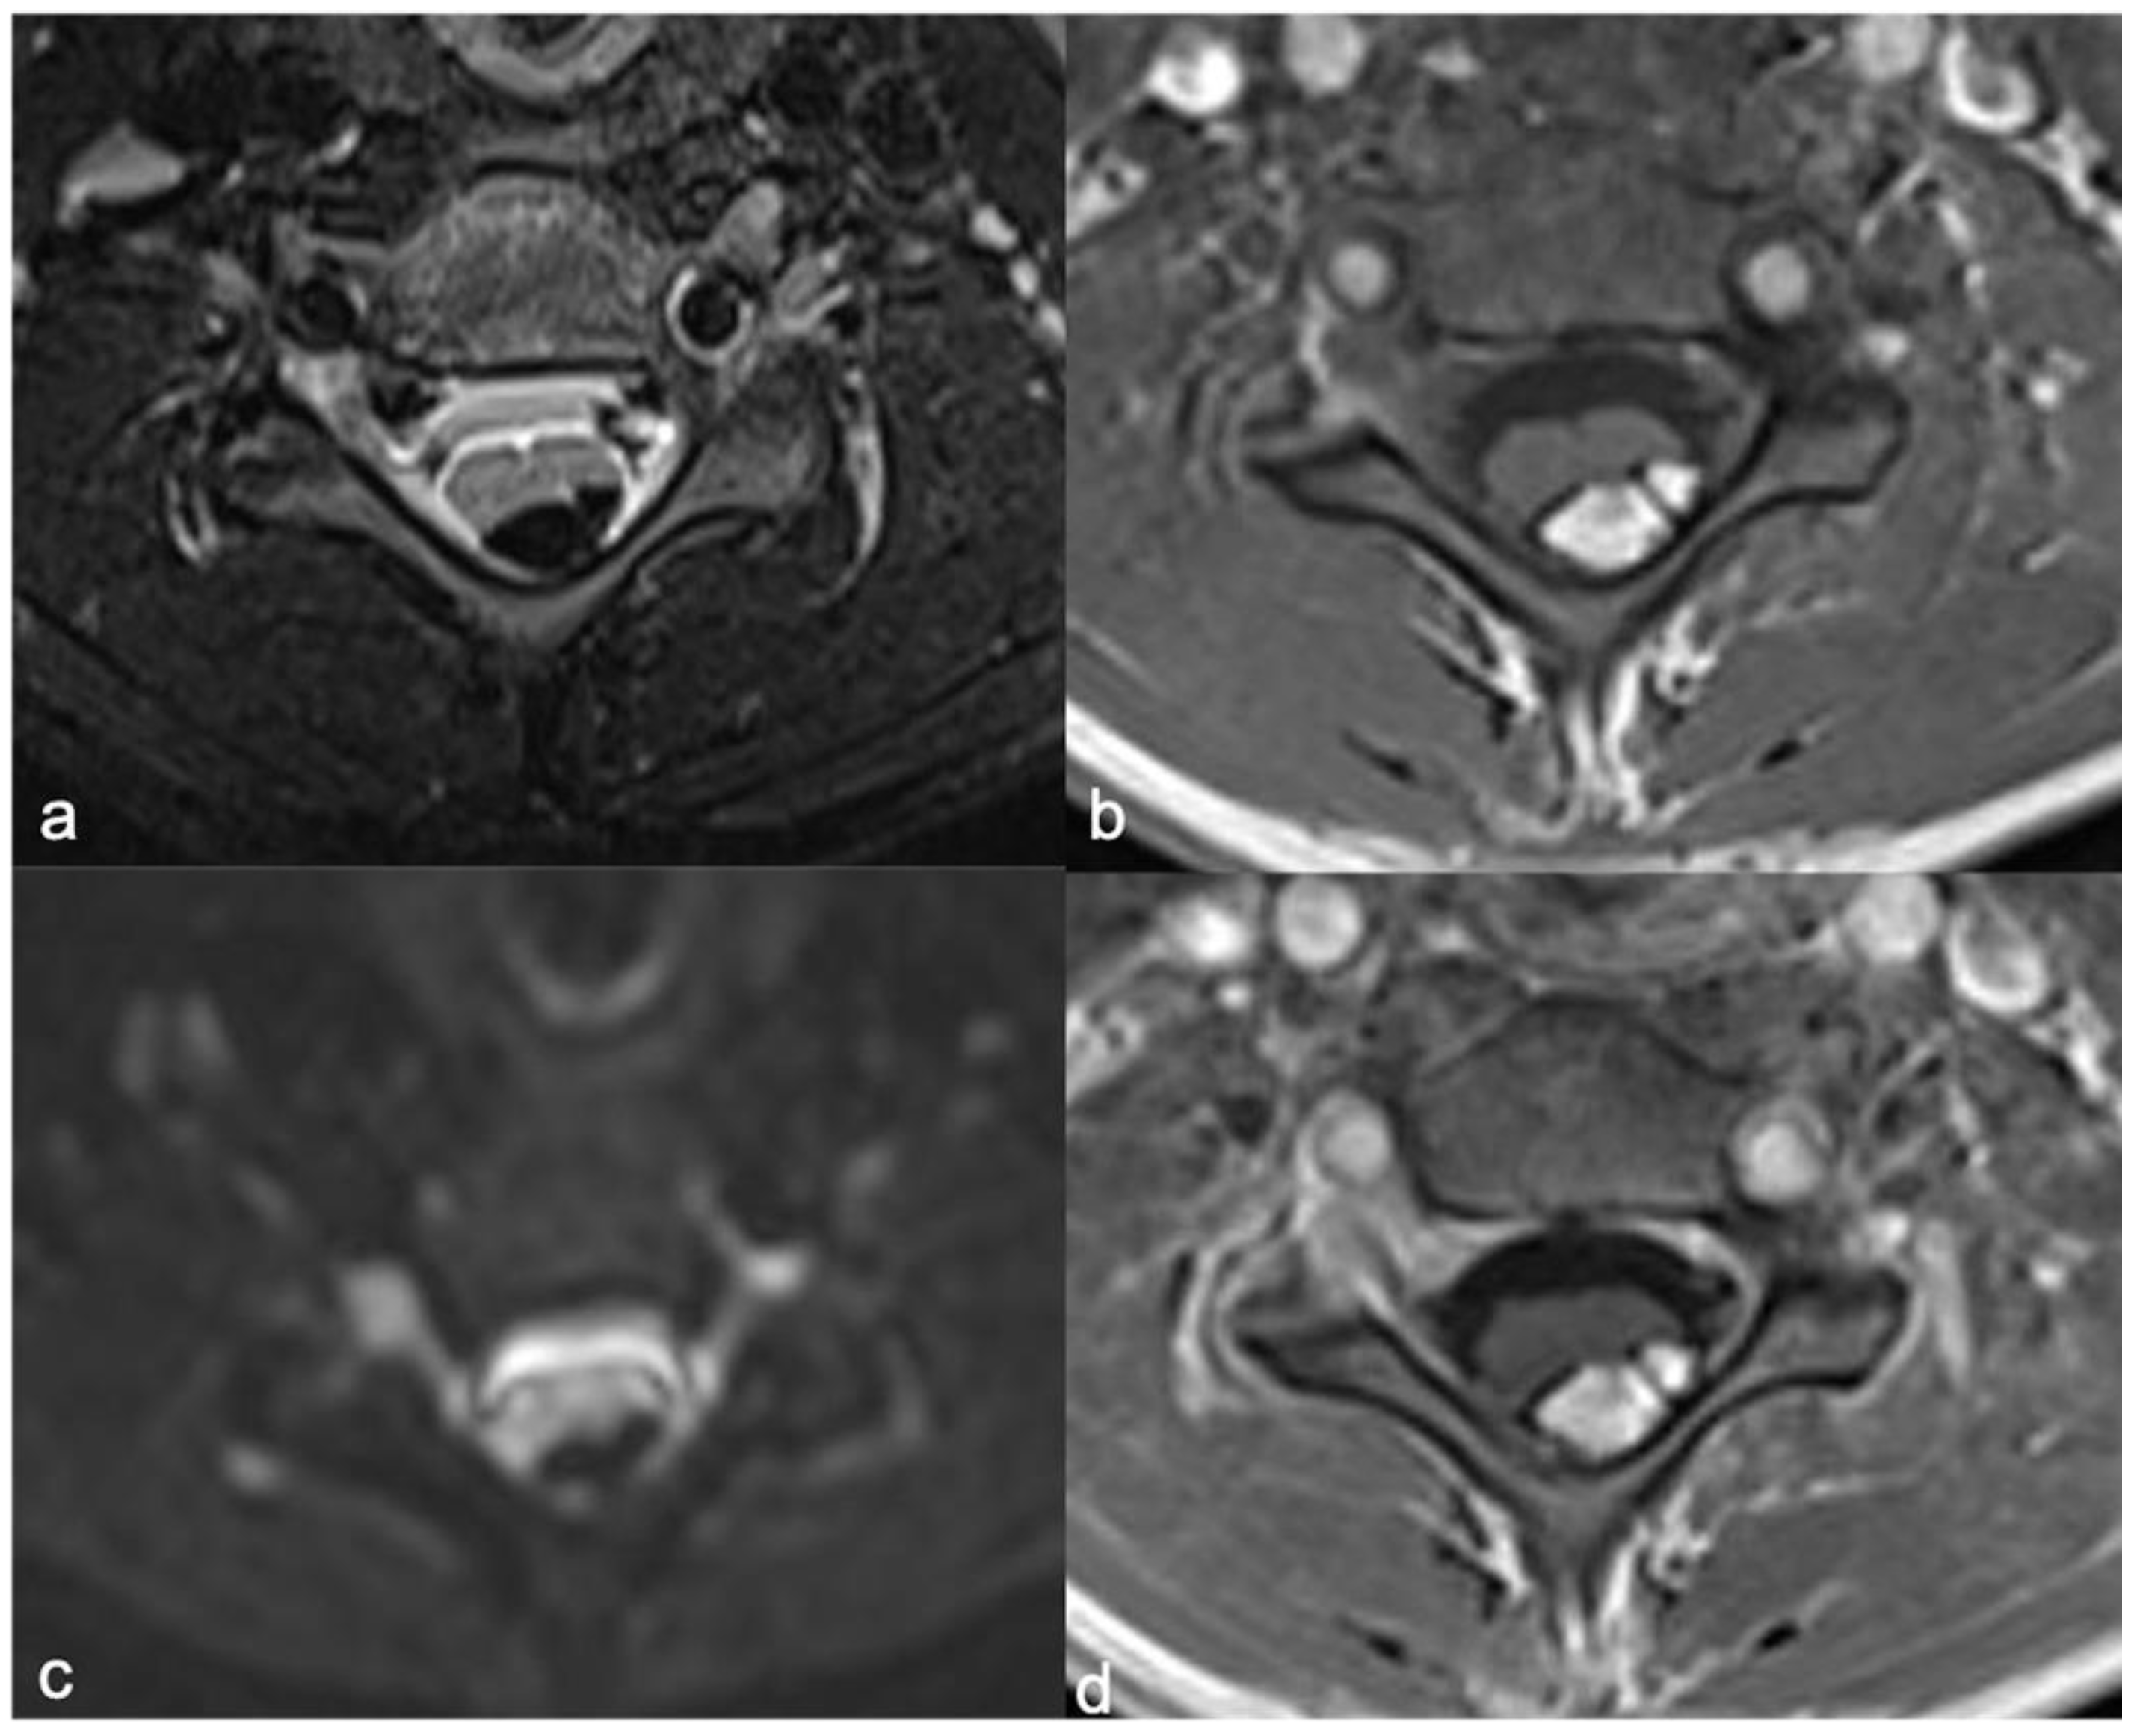

4.1. Hemangioblastomas